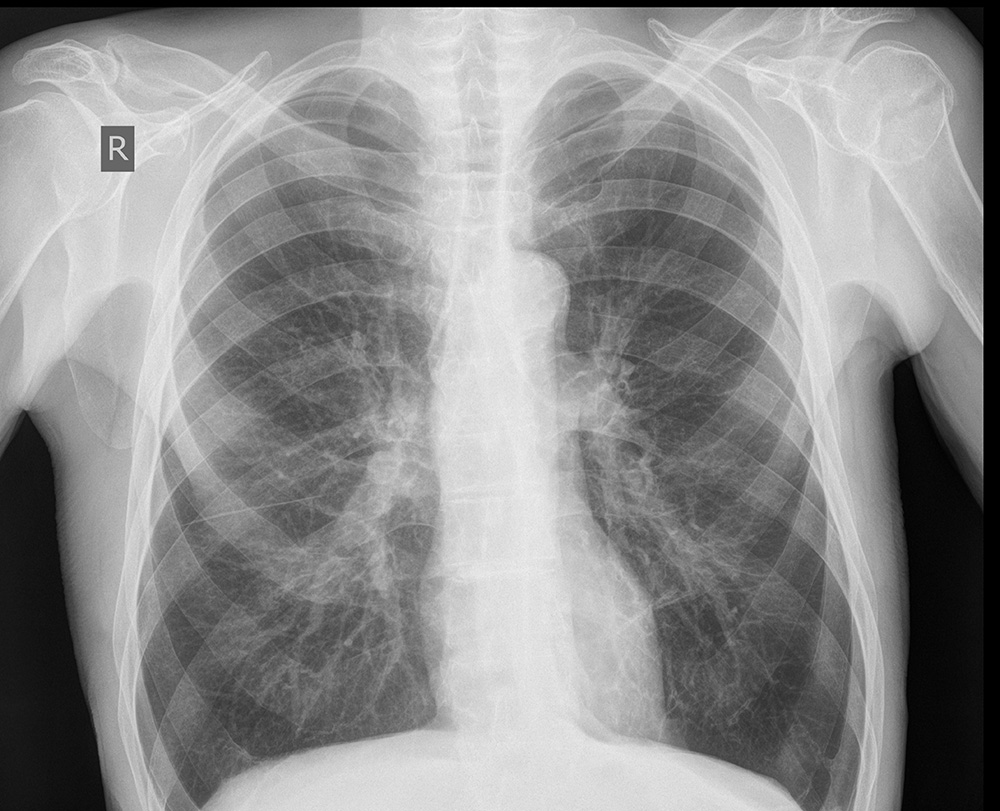

На обзорной рентгенограмме органов грудной клетки в прямой проекции – грудная клетка обычной формы. Легочные поля прозрачные, легочной рисунок не усилен. Корни легких не расширены, структурные. Синусы свободные, Купола диафрагм ровные. Рёберные промежутки не расширены, расположение ребер обычное, слева имеется перелом 5-го ребра по подмышечной линии без смещения. Тень сердца обычной формы, в поперечнике не расширено, аорта не широкая, уплотненная в области дуги - краевой кальциноз.